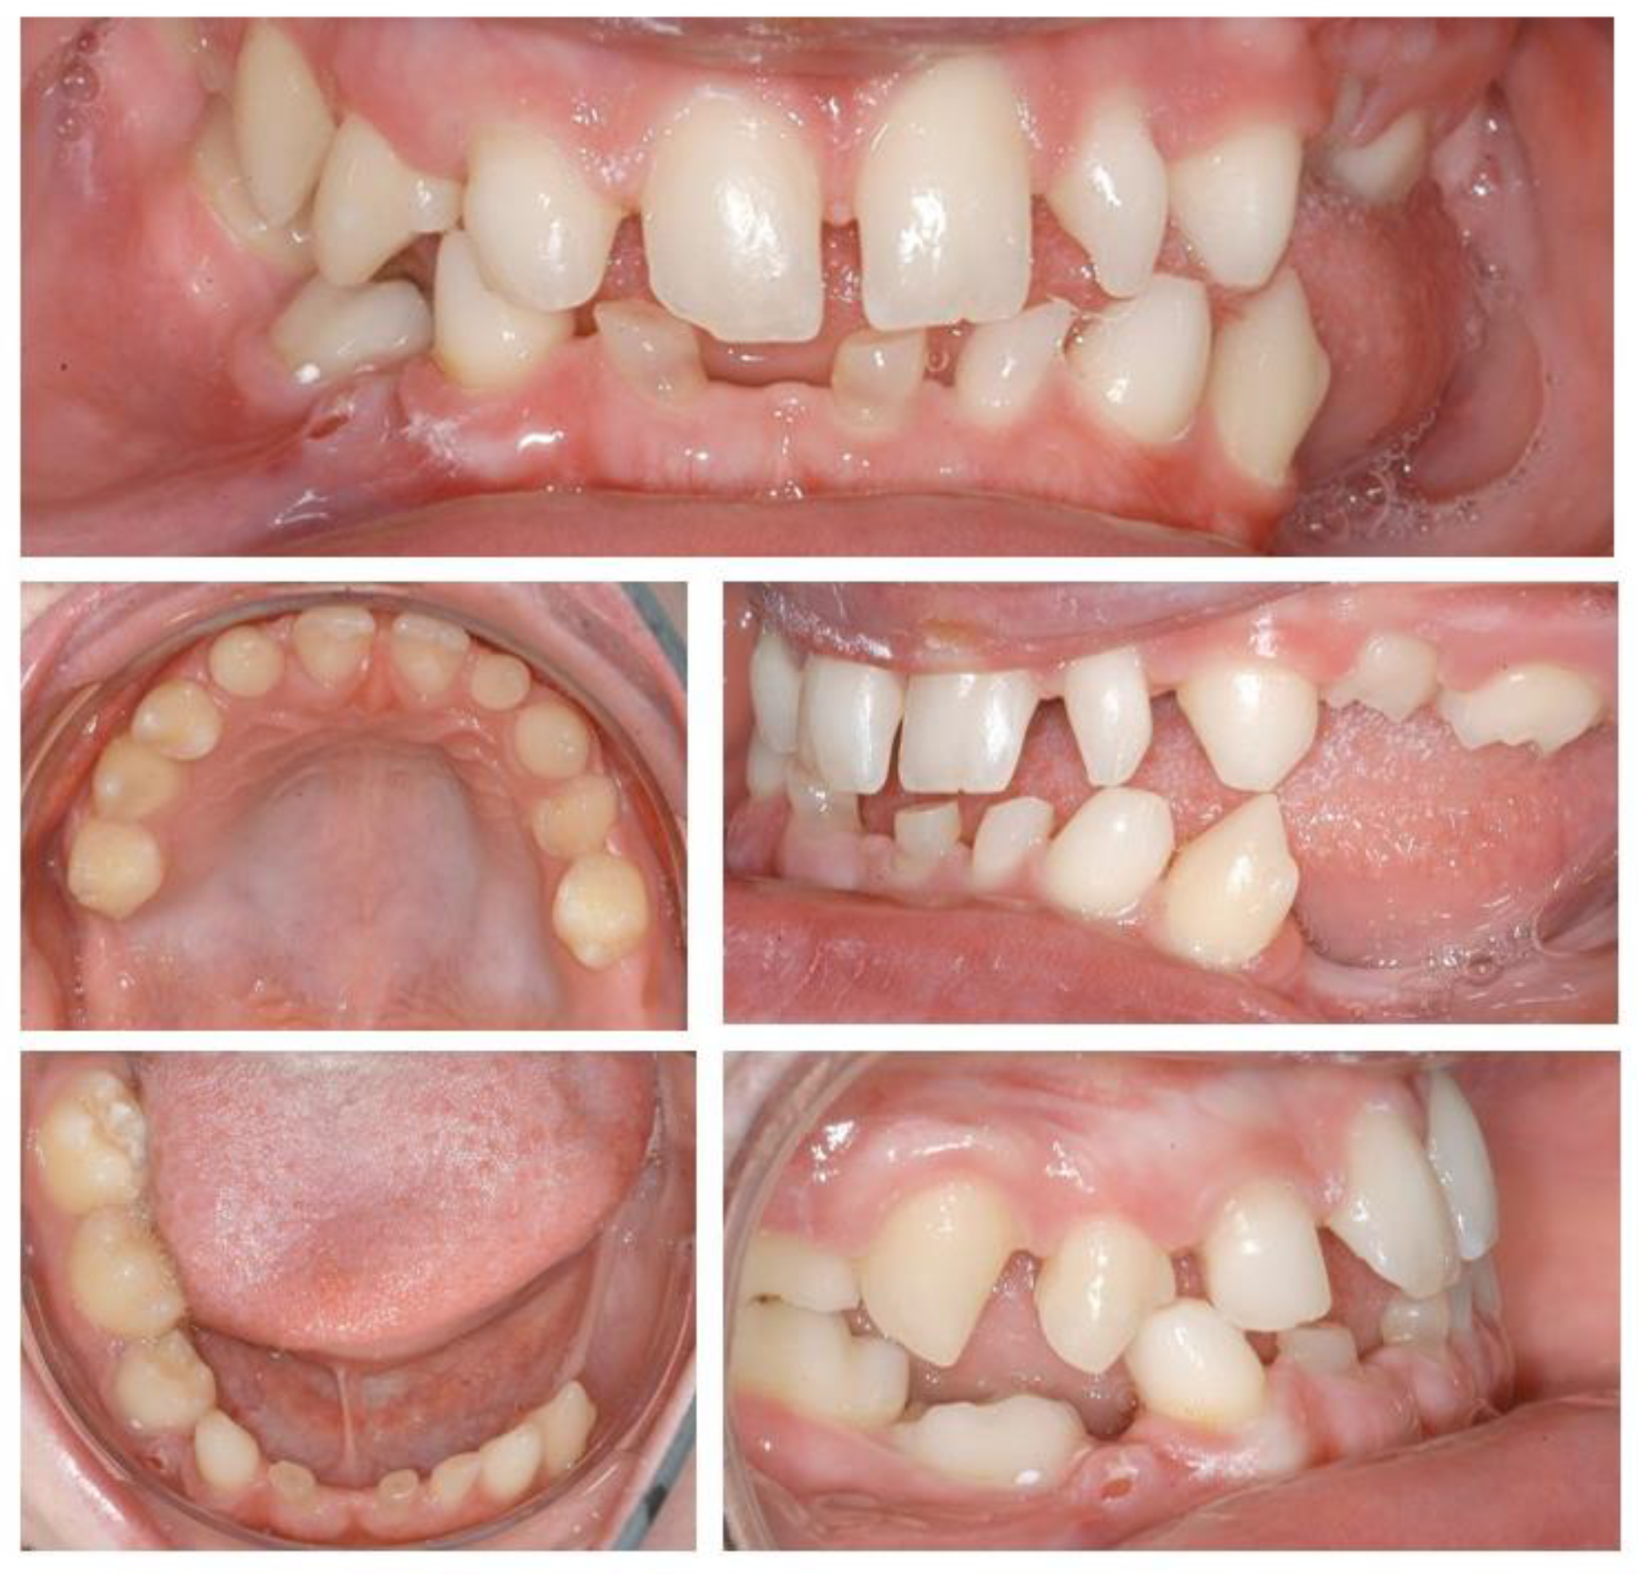

Figure 1.

Initial situation. Clinical examination showed absence of permanent teeth and persistence of primary dentition, abnormally shaped teeth, and unsatisfactory jaw relationship, suggesting the need of interdisciplinary treatment.

A 15-year-old patient attended the Dental Clinic of Hospital University Münster with aesthetic and functional complaint. Medical history and anamnesis revealed a diagnosis of Bloch–Siemens–Syndrome, Incontinentia pigmenti, and Epilepsy, which was previously confirmed by genetic testing. At the time of the consultation, the patient presented good health conditions. Extra-oral examination showed inadequate jaw relationship and loss of vertical dimension. Intra-oral and radiological examinations showed permanent tooth agenesis, and permanence of primary dentition, such as abnormally shaped teeth.

As soon as the orthodontic treatment was completed, the patient returned for dental implant planning. Regardless of adequate teeth alignment, the wide interproximal spaces, disproportional teeth dimensions, and abnormal occlusion increased the complexity of the case (Figure 1). Radiological examinations showed a reduced bone height at the edentulous site. In consideration of a bone atrophy in the upper and lower jaws, a two-stage surgical procedure was planned, which included bilateral sinus lift, nerve lateralization and placement of dental implants at the sites 16, 15, 12, 22, 35, 36, 32, 42, and 45 (Figure 2).